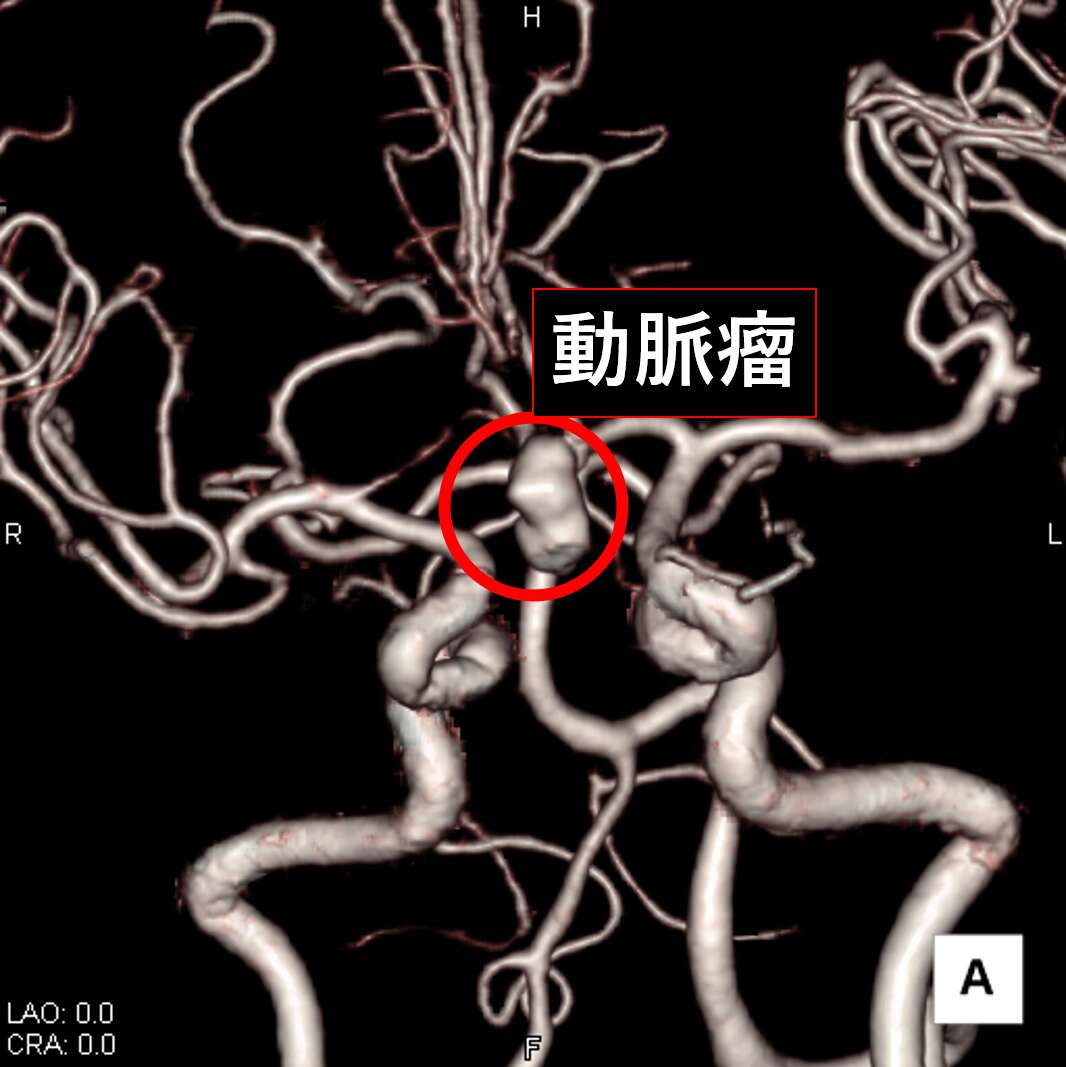

造影剤を用いて撮影すると、臓器や血管の3次元画像を作成することができます。3次元画像では、あらゆる角度から立体的に観察することができ、診断・治療に用いられています。

脳血管 3次元画像

図中の赤丸は腹部の大動脈が「瘤状」になっていることが分かります。

3次元画像にすることで動脈瘤の大きさ、形状、他の臓器や血管との位置関係が把握しやすくなります。